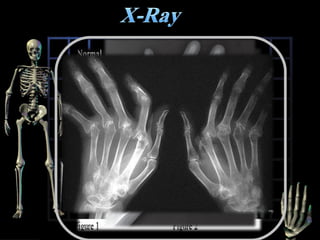

X-Ray of both hands and wrists and feet for

suspected RA.

 X-ray change

Loss of joint space

Soft tissue swelling

Bony decalcification

Erosions

Peri-articular osteoporosis